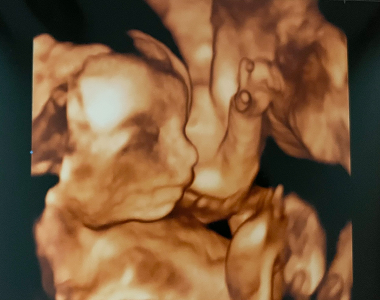

Petra (29. týden těhotenství)

Ve středu mi Petruška odjela na hory s babičkou a dědou, tak jsem alespoň ještě pár dní nemusela extra nic dělat a mohla jsem jen odpočívat pod dekou. Jsem z těch antibiotik taková nervózní, pořád si sahám na bříško a čekám, kdy mě malý Ondrášek kopne, abych věděla, že je v pořádku. Chudáček je teď v bříšku jak na trampolíně, ten kašel je úporný a musí ho vyčerpávat stejně jako mě.

V následujícím týdnu mě konečně čeká kontrola u doktorky na gynekologii. Moc se těším, až malého po dlouhé době uvidím.